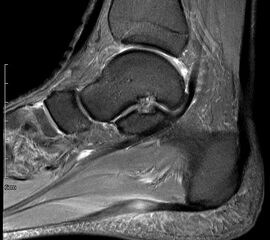

Abbildung 1: Plantarer und dorsaler Sporn im Röntgenbild und im MRT

Abb. 1a und Abb. 1b: großer dorsaler Fersensporn und ein minimaler plantarer Sporn, Patient, 50 Jahre.

Abb. 1c: Bild eines isolierten großen plantaren Fersensporns. Patientin, 32 Jahre.

2.3. MRT

Eine Kernspinuntersuchung erlaubt eine Feindiagnostik des Tarsaltunnels, bei hoher Auflösung können Sehnen, Nerv, Arterie und Venen sowie Veränderungen der Plantarfaszie selbst oder des Faszienursprungs mit Signalalterationen dargestellt werden. Aufgrund der Sensitivität des Verfahrens kann unterschieden werden, ob es sich um eine Veränderung des Ursprungs der Plantarfaszie oder um eine weiter distal gelegene Problematik handelt. Gelegentlich findet man auch Teilrupturen etwas distal des Ansatzes (siehe Abb. 2). Diese Methode erlaubt auch eine Aussage über knöcherne Veränderungen.

Abb. 2: Teilruptur Plantaraponeurose in der MRT Diagnostik

Eine Teilruptur der Plantaraponeurose kann ursprungsnah oder auch einige cm distal des Ursprungs als Folge einer direkten Gewalteinwirkung auftreten.